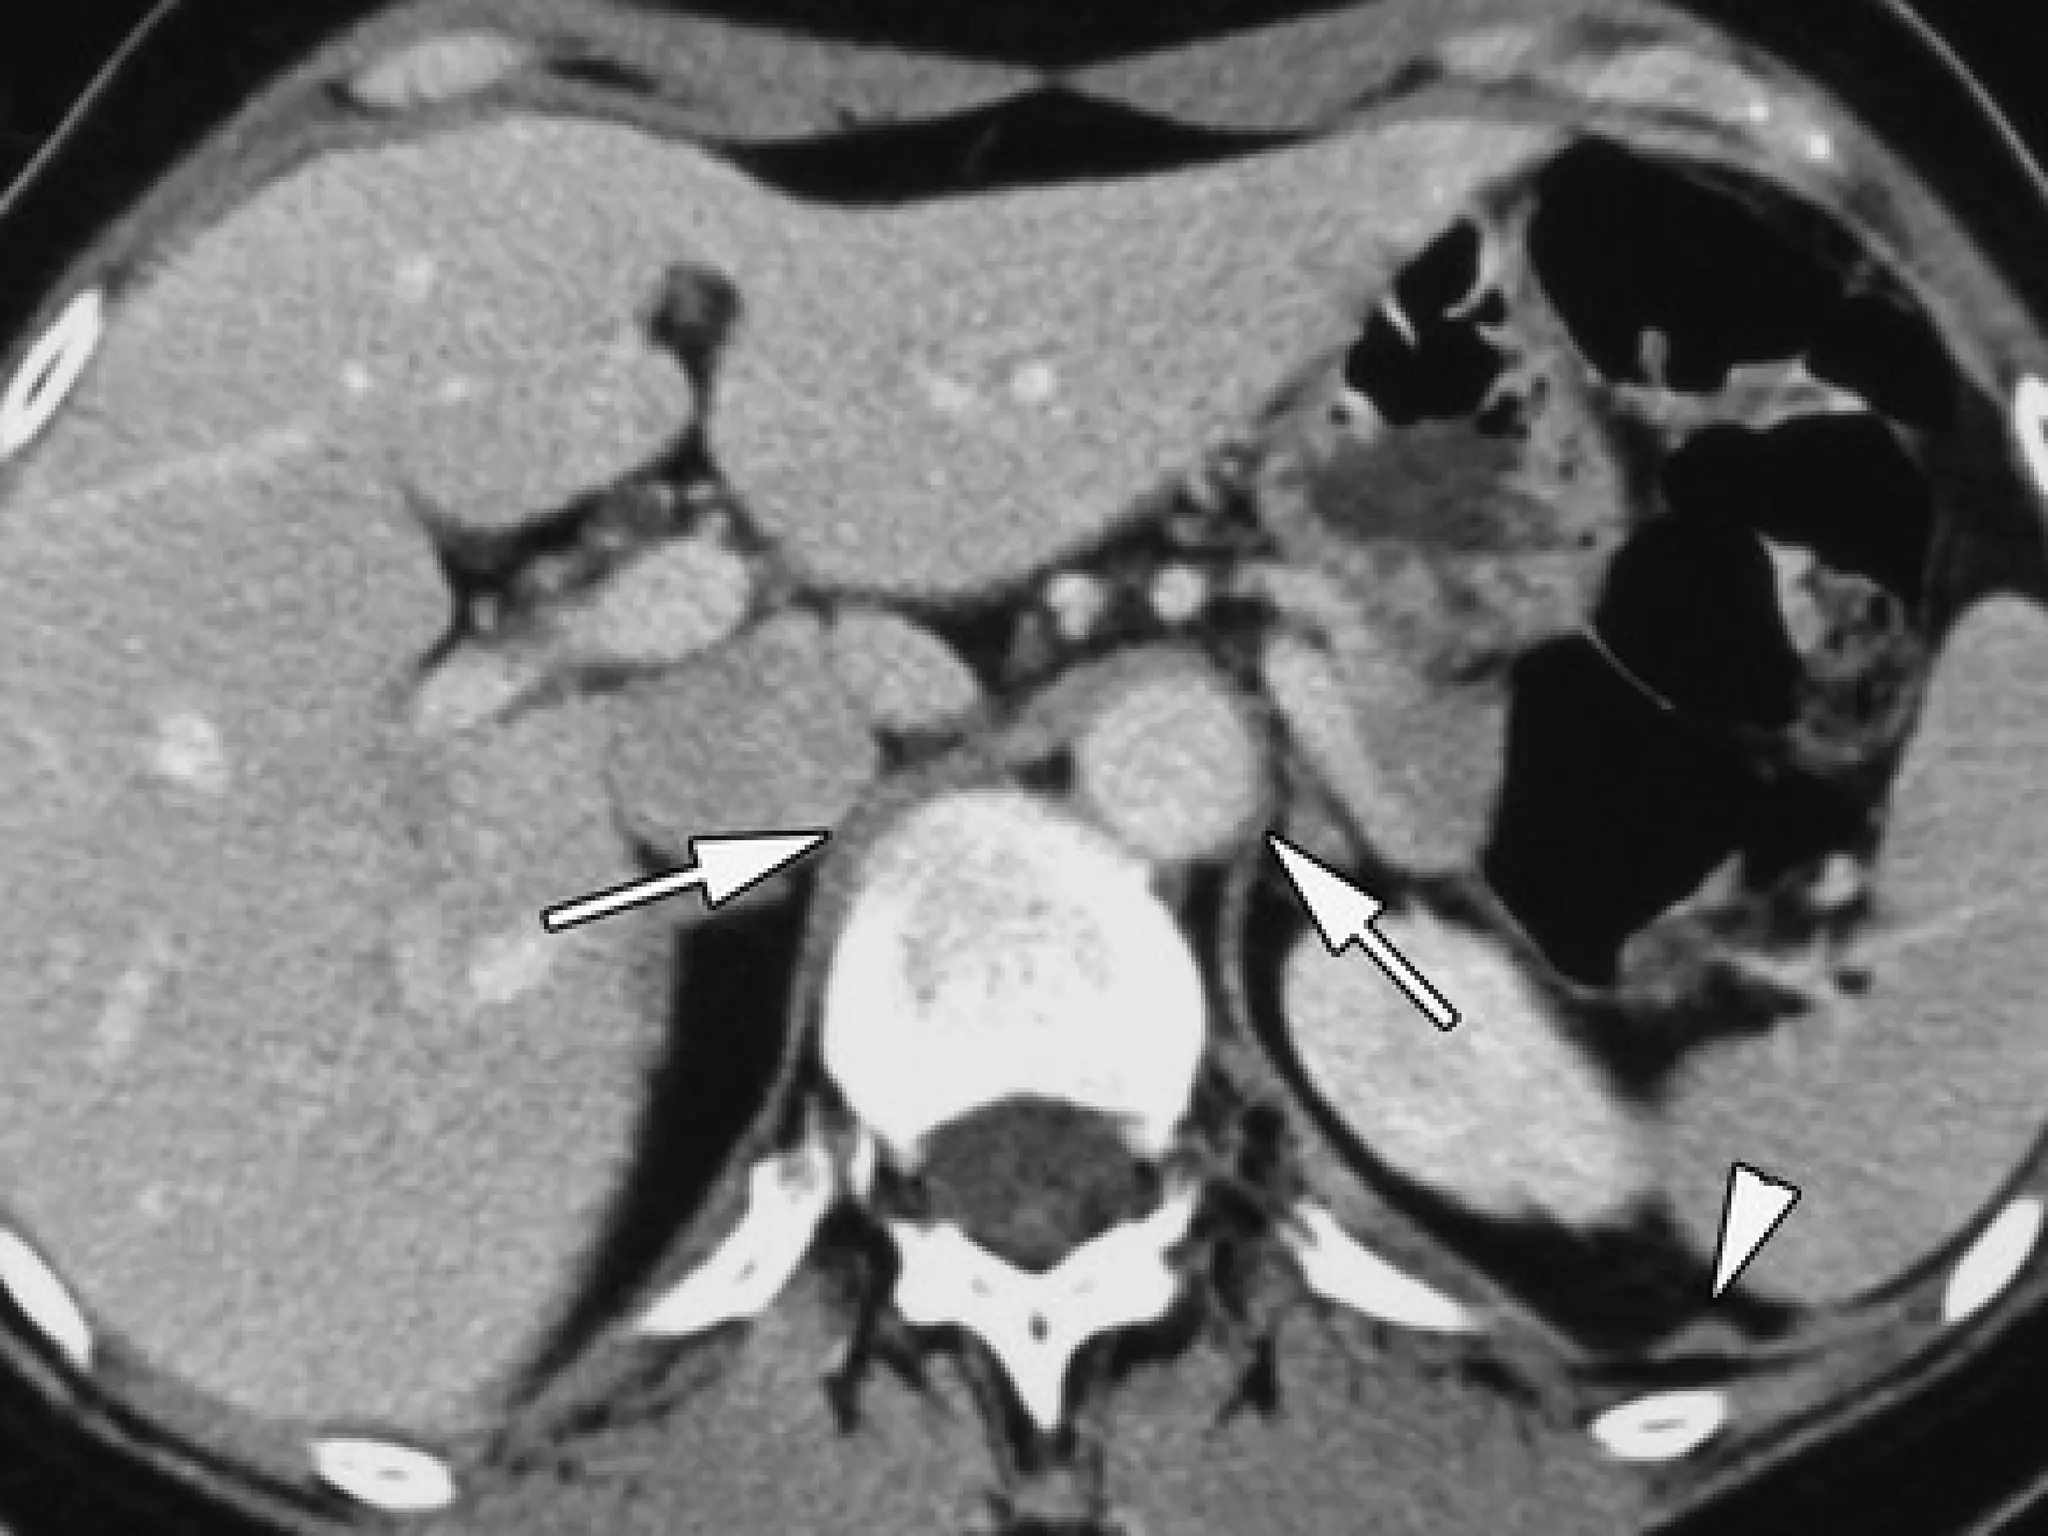

 Direct discontinuity

Direct discontinuity of the hemidiaphragm:

of the hemidiaphragm:

sensitivity 73%, specificity 90%.

 Intrathoracic herniation of abdominal contents:

Intrathoracic herniation of abdominal contents:

sensitivity 55%, specificity 100%.

 The

The collar sign

collar sign:

:

sensitivity 36% with conventional CT

63% with helical CT

– On the right side, the collar sign can appear as a focal

On the right side, the collar sign can appear as a focal

indentation of the liver, a subtle sign easily overlooked

The dependent viscera sign

dependent viscera sign:

sensitivity: 100%: left-sided

83%: right-sided